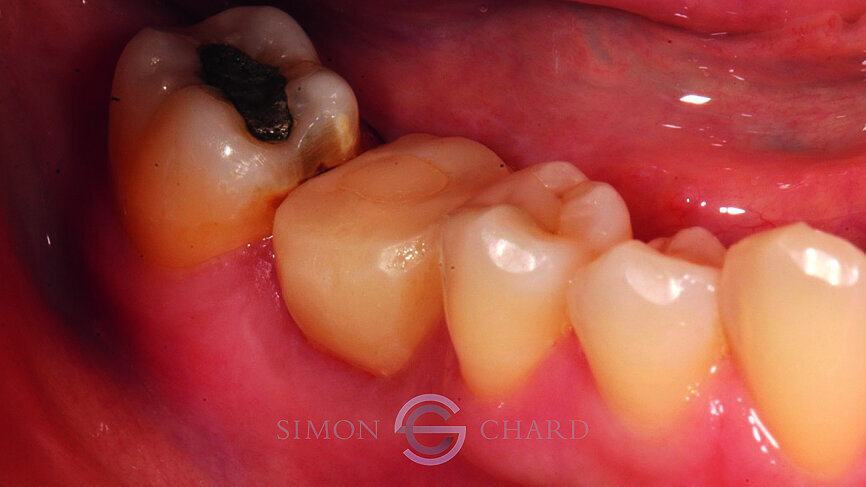

This case report highlights a novel method of restoring implants utilising the modern advances in digital intraoral scanning and chairside milling. It illustrates how an aesthetic single implant retained crown can be provided chairside without the need for analogue impressions (Figs. 1 & 2: Pre-operative condition).

Following a discussion of the options for replacement of LR6, the patient elected for an implant-retained solution. A MegaGen AnyRidge 4 x 10 mm implant was placed utilising a surgical guide for position of the pilot hole. An immediate temporary crown was fabricated using the MegaGen fuse abutment and DMG Luxatemp. A silicone index of the diagnostic wax-up was fabricated and the temporary crown was polished and taken out of occlusion while the implant fully integrated (Fig. 3).